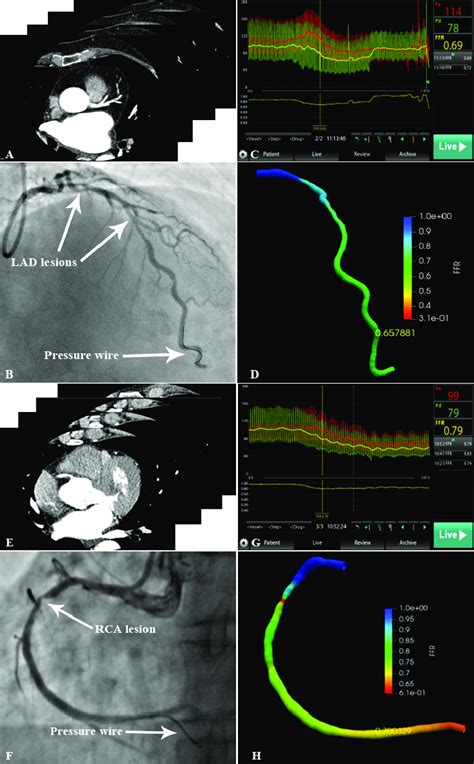

Alright guys, let’s start with the big question: what is an FFR-CT scan? FFR stands for Fractional Flow Reserve, and when we add ‘CT’ to it, we’re talking about a revolutionary way to assess the severity of blockages in your coronary arteries. Traditionally, to figure out how much a blockage was actually restricting blood flow, doctors would need to perform an invasive procedure called a cardiac catheterization. This involves inserting a thin tube (a catheter) into an artery, usually in your wrist or groin, and guiding it all the way to your heart. Then, they’d inject dye and take X-rays to see the arteries. To measure the FFR, they’d then insert a special wire across the blockage to measure pressure differences. It’s effective, for sure, but it’s invasive, requires anesthesia, and has its own set of risks. The FFR-CT scan, on the other hand, is a non-invasive game-changer. It uses advanced computational fluid dynamics and your standard CT scan data to create a 3D model of your heart and its arteries. This model then allows sophisticated software to simulate blood flow and pressure. Essentially, it’s like having a virtual wind tunnel for your heart’s arteries, telling us exactly where the problem areas are and, more importantly, how much they’re impacting blood flow, all without needing to stick anything inside you. Pretty neat, huh? This technology is transforming how we diagnose and manage coronary artery disease, offering a safer and often more efficient pathway to diagnosis and treatment decisions. It bridges the gap between simply seeing a blockage on a CT scan and understanding its functional significance – that is, how much it’s really bothering your heart’s blood supply.

Curious about the magic behind the FFR-CT scan? Let’s walk through it. It all starts with a special type of CT scan called a coronary CT angiography (CCTA) . This isn’t your average chest X-ray, guys. You’ll likely be given a contrast dye through an IV, which helps highlight your coronary arteries on the scan. The CT scanner takes incredibly detailed, rapid images of your heart as it beats. Think of it as taking thousands of high-speed photos from every angle. Once we have these high-resolution images, the real wizardry begins. The CCTA data is then sent to specialized software. This isn’t just any software; it’s powered by complex algorithms and computational fluid dynamics (CFD) . CFD is a branch of physics that uses mathematical equations to simulate how fluids – in this case, blood – move and behave. The software takes the 3D anatomical information from your CT scan and essentially builds a virtual replica of your coronary arteries. It then simulates the blood flow through these arteries, taking into account factors like the shape and severity of any narrowings, the heart’s pumping action, and even the resistance in the smaller blood vessels downstream. By analyzing the pressure and flow rates at different points in the arteries, the software can calculate the FFR value for any given point. An FFR value of 1.0 means there’s no pressure drop, indicating normal flow. As the FFR value decreases (e.g., below 0.80), it signifies a significant blockage that’s impeding blood flow. This entire process is done virtually, on a computer, using the data from your scan. So, you lie down for a CT scan, and the FFR calculation happens later, in the digital realm. It’s a fantastic example of how advanced computing and medical imaging are coming together to provide deeper insights into our health.